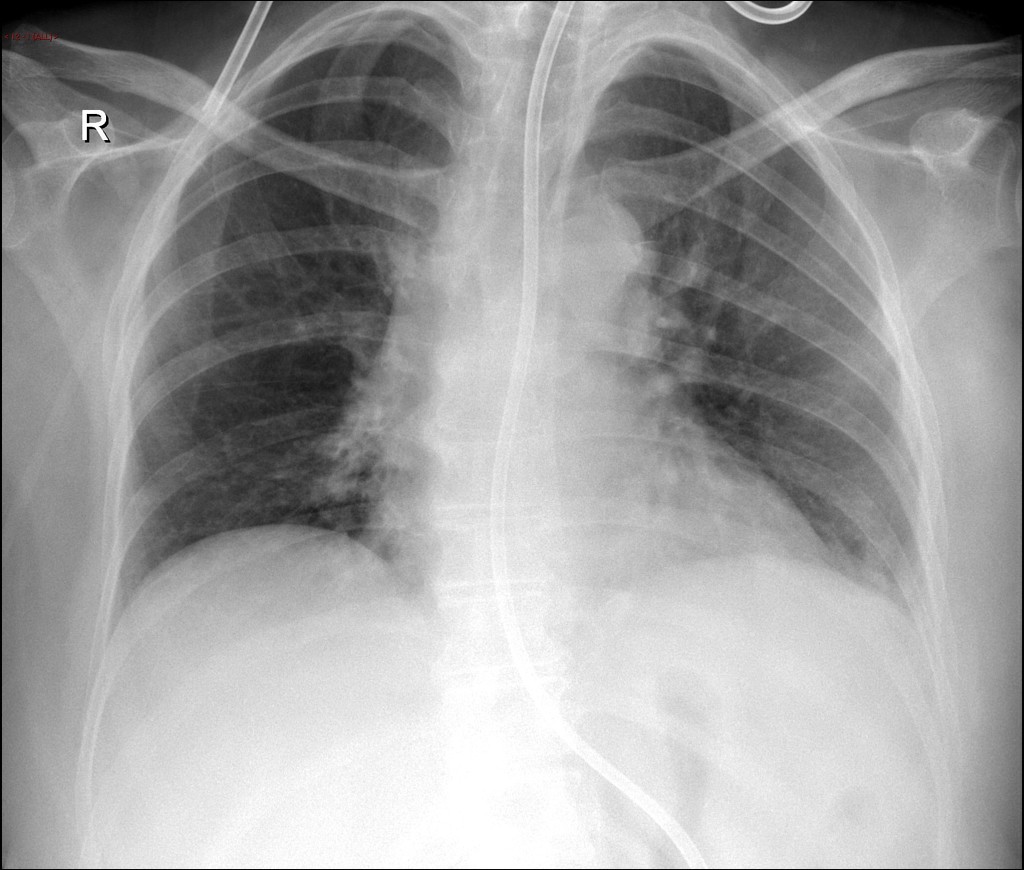

Click vào ảnh để xem 5 hình ảnh minh họa

Điều trị Mediastinitis hay Trung thất là Xét nghiệm máu toàn bộ (CBC), xét nghiệm bảng chuyển hóa toàn diện (CMP), chụp cắt lớp vi tính (CT Scan), chụp cộng hưởng từ (MRI), điện tâm đồ (EKG), xét nghiệm Tronopin, chụp X-quang, cấy máu.